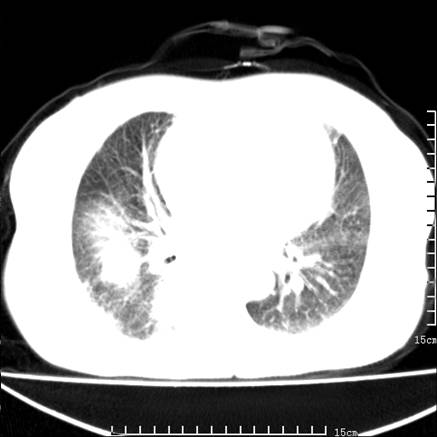

女,王某,58岁,咳嗽三个月余,基层医院二个月前诊为肺结核,用抗结核药二个月无明显疗效。

心包积液致肺瘀血.右侧周围型肺癌伴肺内转移,中间裂积液,叶间胸膜肥厚.右上肺大泡,右侧胸膜肥厚.

双肺继发型tb,心功能不全并肺淤血、心包、双侧叶间裂积液,肺大泡,右下胸膜肥厚钙化。